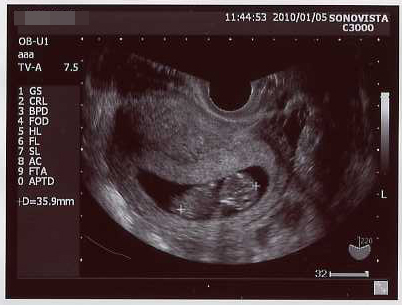

今日は検診でしたー

前回の倍の3.6センチに成長。

なんか劇的にでかくなった気がする!子宮の中いっぱいになってきたw

クリックで拡大。

今までのエコーも並べてみた →エコー写真

前回は、粘土の固まりにポコポコ手足をくっつけたみたいな形だったのが、

今回、首のくびれが出来、手足も伸びて、お人形さんみたいだった!

イヤーンて、寝返り打ちたいような感じで動いた姿が見れたのが嬉しかった。

こんなちっちゃい内から、胎動してるんだね~

心音も聞かせて貰った、今の心拍はオトナの倍位の速さだそうです(*´ω`)